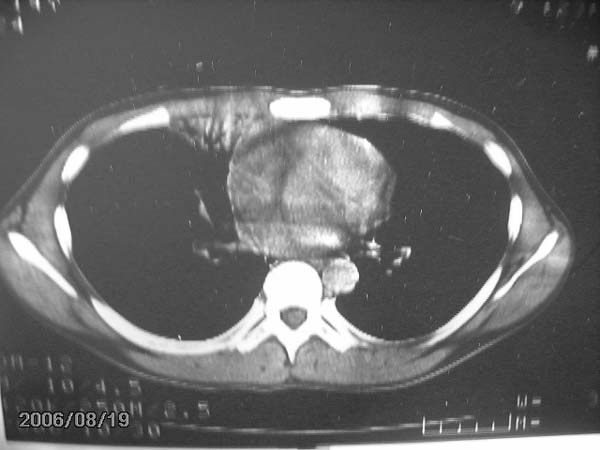

男,13岁,发烧半月,干咳无痰,正规使用抗生素半月,现在仍是午后低烧!!!未做痰检

结合临床考虑:右肺中叶结核可能性大.

右肺中叶结核可能性大

右肺结核,右肺中叶不张

右侧肺门淋巴结好象有增大,会不会是个原发综合症合并感染

右中肺呈大片状密度欠均匀影,内见含气支气管.

结合病史,考虑:右中肺大叶性肺炎(吸收期).

右肺中叶大片状密度增高影,内密度不均匀,右肺门处增大,应该是淋巴结肿大,结合临床首先考虑原发性肺结合可能性大,不排除合并感染可能,建议治疗后复查.

考虑中叶综合征(右肺门肿大淋巴结伴中叶阻塞性炎症)